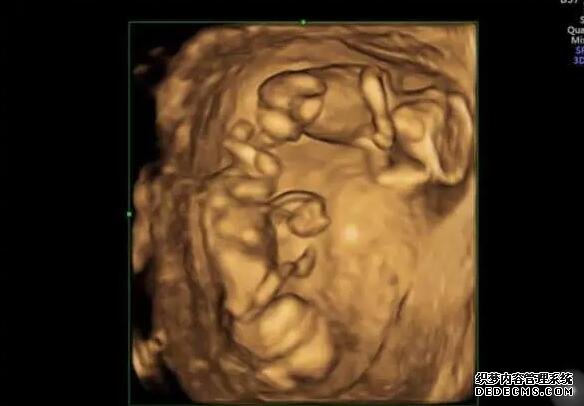

試管移植是一種輔助生殖技術,是許多不能自然懷孕的夫妻選擇的方法。在試管移植過程中,女性需要注射人工促排卵藥物來促進卵巢排卵。而在移植當天,打一針促黃體生成素能夠幫助維持黃體功能,增加著床成功率,從而提高受孕率。